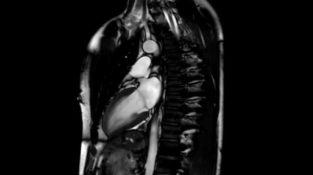

O inimă umană pe un scaner RMN

Urmăriți o inimă pulsantă înregistrată de un scaner RMN de înaltă rezoluție. Videoclipul a fost realizat cu voluntarul ținându-și respirația, astfel încât plămânii să rămână imobile.